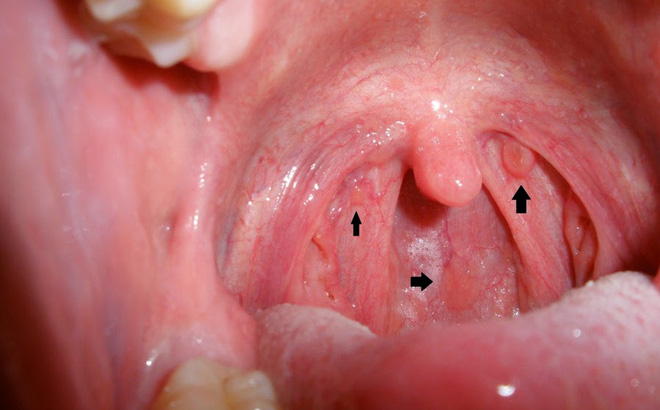

Xét nghiệm sợi quang (Fiber-optic), sinh thiết tế bào vòm họng để xác định chẩn đoán.

Click vào ảnh để xem 4 hình ảnh minh họa